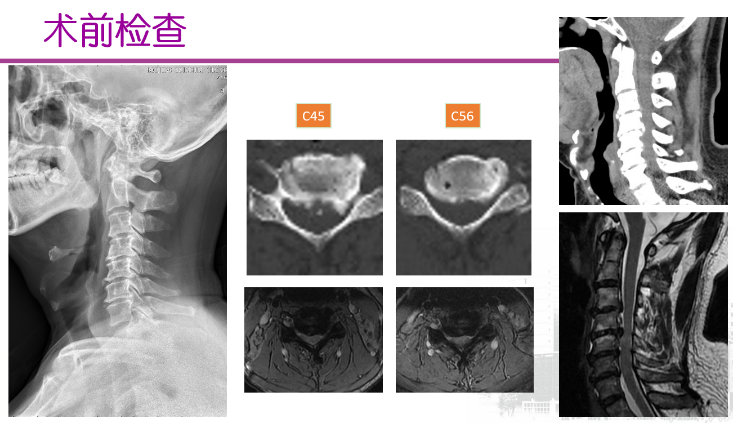

图2 王劲教授--精准微创治疗颈椎病